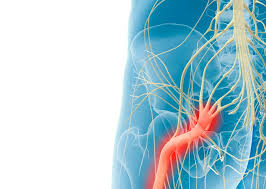

Download Sciatic nerve pain pictures